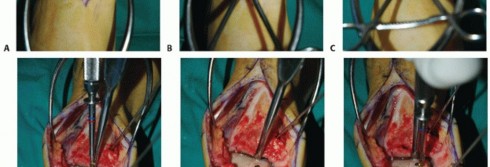

Anterior approach (TECH FIG 6)

Similar to anterior approach for ankle arthrodesis and total ankle arthroplasty Protect the superficial peroneal nerve.

Divide the extensor retinaculum over the extensor hallucis longus tendon. Protect the deep neurovascular bundle.

Anterior capsulotomy, unlike ankle arthrodesis and total ankle arthroplasty, must protect ankle cartilage.

Expose OLT with plantarflexion. Assess mediolateral dimensions and attempt to assess AP dimensions.

Make a vertical (sagittal) cut in the talus 1 mm lateral to the lateral extent of the OLT. The depth of this cut

should be conservative until the exact superior to inferior dimensions of the OLT can be mapped out on the talus (TECH FIG 7A).

Horizontal (axial) resection in the talus (TECH FIG 7B)

To maintain the proper axis, we routinely use a Kirschner wire placed from anterior to posterior, with its trajectory and depth confirmed on intraoperative fluoroscopy, to avoid misdirection of the axial resection.

We use a thin oscillating saw for this cut and also with cold saline irrigation to cool the blade in an attempt to avoid heat necrosis to the bone.

- TECH FIG 6 • Anterior approach, similar to that performed for total ankle arthroplasty. Because the entire medial one-third to one-half of the talar dome will be restructured, a medial malleolar osteotomy is typically not necessary.

Protect the medial malleolar cartilage. Consider using a malleable ribbon retractor in the medial gutter.

Extract the resected bone (TECH FIG 7C,D).

Revisit the vertical and horizontal resections with the saw, a rasp, or both. If there is residual OLT in either

or both of the prepared surfaces, then consider curetting these and bone grafting or resecting more native talus (TECH FIG 7E).

Fluoroscopic evaluation sometimes affords a useful appreciation of the recipient site. Determining the exact dimensions of the recipient site:

Calipers (TECH FIG 7F) Ruler (TECH FIG 7G)

- TECH FIG 7 • A-D. Preparing the recipient site. A. Sagittal cut with reciprocating saw. B. Axial cut also with reciprocating saw. C. Elevating diseased portion of talus with osteotome. (continued)